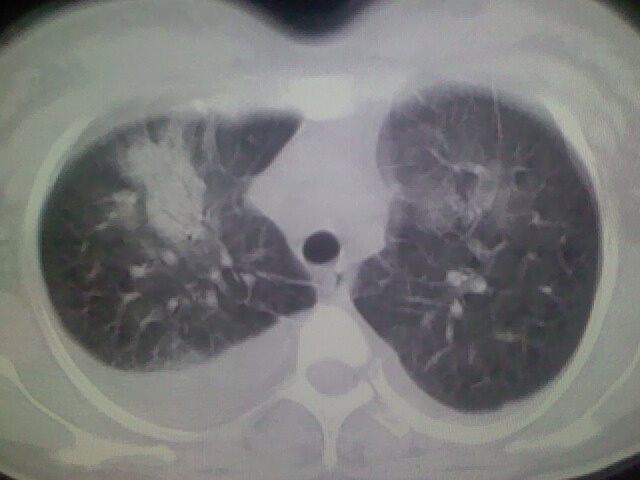

女,24,剖腹产后,突觉胸痛,干咳,不能平卧

胸水 感染 心影增大 肺水肿?

双肺“肺泡性肺水肿” “胸腔积液”!

双侧胸腔积液,肺泡性肺水肿。后纵隔好像有占位。

考虑肺梗塞、肺水肿,双侧胸腔积液

肝脾大,双侧胸腔积液,双肺水肿,肺动脉[包括远端小动脉],左右心房,左心室增宽,右心室主动脉无明显改变,符合左心功能不全征;;建议除外二尖瓣关闭不全,扩张性心肌病